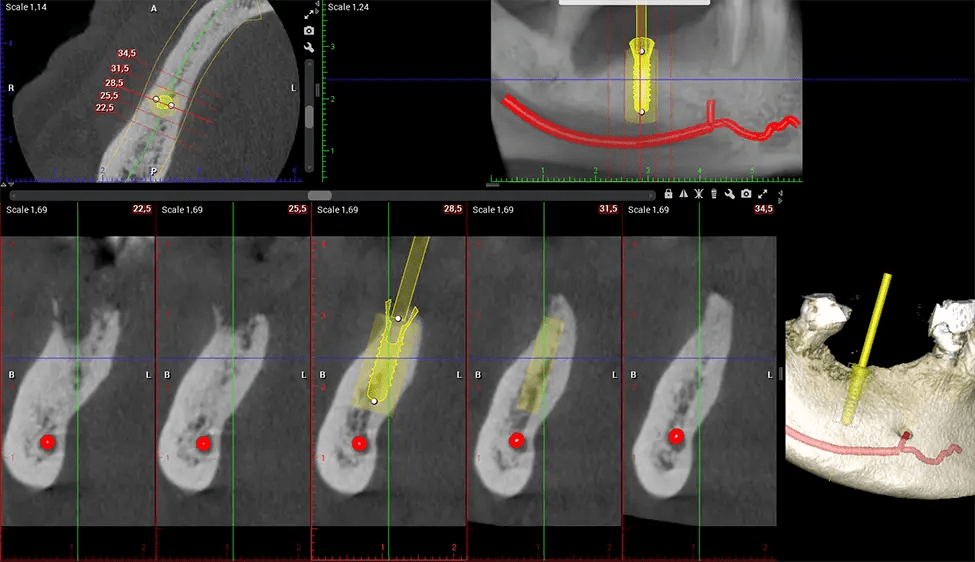

Oral and Maxillofacial Surgeon Complex oral surgeries, orthognathic (jaw) surgery, and removal of impacted teeth. Offers precise, three-dimensional visualization of the skull, jaw, and craniocervical junction to enhance diagnostic accuracy and minimize surgical risks.

There are many benefits to using CBCT technology, especially compared to the traditional 2D X-ray format. One of the most significant advantages of CBCT scans is that they provide much more information than traditional X-rays. A scan lets your dentist see images from all angles of your jaw and mouth, including your sinuses, nasal cavity, cheekbones, and other surrounding areas. This added information helps your dentist craft a comprehensive treatment plan that addresses all aspects of your oral health.

Another significant benefit is that 3D imaging provides more precise images of your bone structure. These images are more detailed, providing you with a more accurate diagnosis. An accurate diagnosis means better treatment for you.

When paired with extractions, dental implant placement, or bone grafting, CBCT technology can provide you with a quicker and much more comfortable experience. This is because the 3D image provides a more detailed picture of your entire oral cavity, allowing your dentist to walk you through each step of the process before it occurs. This often helps patients feel more prepared and comfortable overall, especially if they have had a traumatic experience with past dental treatments.